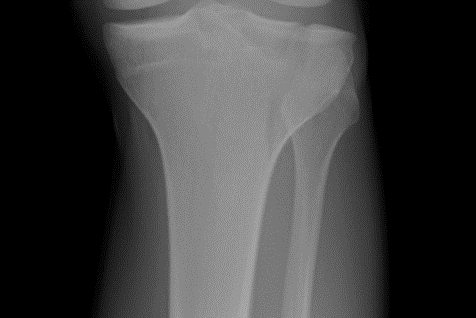

What type of fracture is this?

Straight line down the bone